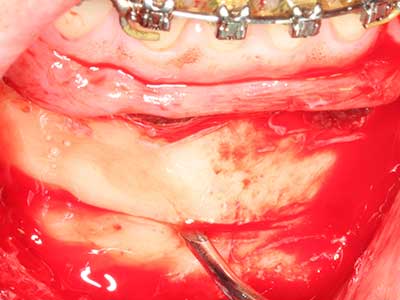

Bei der Knochenblockentnahme zeigen sich weitere Vorteile für die Piezochirurgie: Neben der bereits beschriebenen hohen Präzision bei der Osteotomie stellt sich gerade die Verwendung der dünnen Sägespitzen als besonders materialschonend heraus. Bei der Verwendung insbesondere von Lindemannfräsen sind mit deutlich höheren Entnahmeverlusten durch die dickere Instrumentenspitze zu rechnen (Lakshmiganthan, Gokulanathan et al. 2012). Die insbesondere bei retromolar entnommenen Blocktransplantaten notwendige basale Abtrennung wird durch speziell hierfür vorgesehene rechtwinklige Sägen erleichtert, so dass die Piezochirurgie als präzises, übersichtliches und sicheres Verfahren zur retromolaren Knochenblockgewinnung angesehen wird (Happe 2007) (Abb. 1-12).

Abb. 1: Präparation eines ent-sprechenden Knochendeckels mit dem Piezomed.

Abb. 3: Die basale Abtrennung des Blocks wird durch speziell abgewinkelte Aufsätze erleichtert.